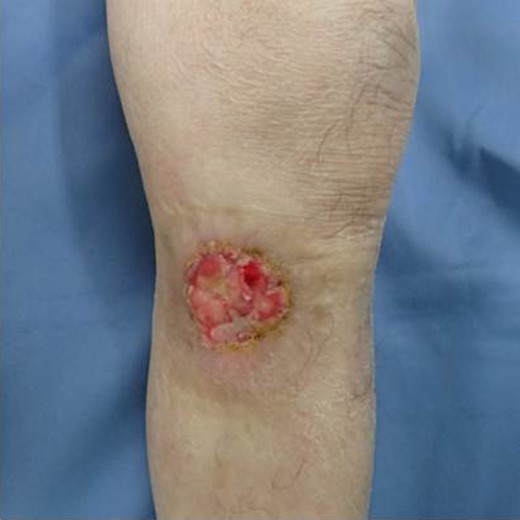

The patient was an 83-year-old male with a granulomatous tumor on his left lower leg. He said that it had existed for about 10 years. An incisional skin biopsy was performed at a neighbor medical institution and histopathologically suggested PCACC. He was introduced to our out-patient clinic. At his admission, the tumor was about 4 cm in the diameter and showed a few red granulomatous nodules (Fig. 1). MRI revealed that the tumor infiltrated subcutaneous tissue but did not reach muscle and bone (Fig. 2). The whole-body PET-CT showed that fluorodeoxyglucose (FDG) accumulated at the tumor area of the left lower leg. FDG also accumulated in the left inguen, however any other accumulation was not defected (Fig. 3). Therefore, it was suspected that the left inguinal hot spot was the metastatic lesion from the PCACC lesion at the left lower leg. At the first operation, the tumor was resected 2 cm far from the tumor margin, including basal muscle fascia and periosteum, and the defect was covered with an artificial dermis under general anesthesia (Fig. 4). At the same time, inguinal lymph node dissection was performed. Histopathological examination of the tumor revealed that cubical cells which had high nuclear-to-cytoplasmic ratio proliferated with cribriform, tubular or cord-like structure in the dermis and subcutaneous tissue. Perineural invasion by the tumor was observed. Metastasis to superficial inguinal lymph node was also histological confirmed (Figs 5 and 6). Most lumens had mucus which was stained by Alcian-blue (AL-B) and Periodic acid-Schiff (PAS) inside of them (Fig. 7). In the immunohistochemical findings, the tumor cells were positive for EMA, SMA, S-100protein, BerEP4, p63 and C-kit (Fig. 8). According to these clinical and pathological findings, the tumor was finally diagnosed the tumor as PCACC. Microscopically, the tumor was resected completely.